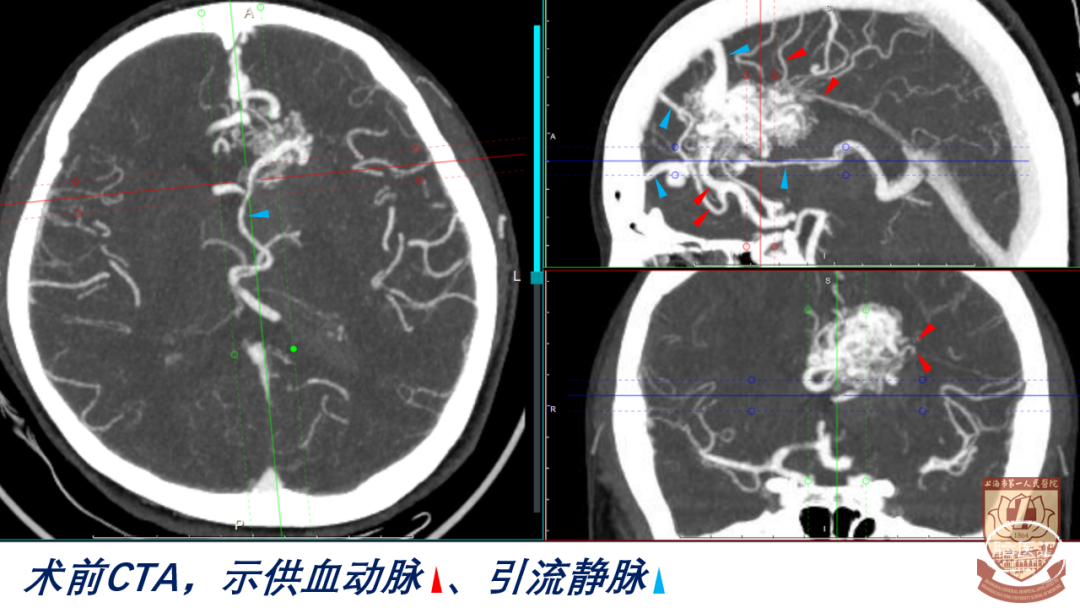

CT:左侧额叶少量出血,脑室系统积血,左额叶内侧稍高密度占位

CTA、DSA:左侧额叶AVM

诊断:左侧额叶AVM破裂出血;S-M分级:IV级(S3V1E0),改良分级II级(A2B0C0)

nidus构筑

供血动脉:三组

前:左侧A3、胼缘动脉

后:大脑中动脉分支、脉络膜后动脉(后胼周动脉)

外:白质穿支动脉

引流静脉:

内侧面:额内侧静脉(前、中、后)

深部:大脑内静脉-Galen静脉